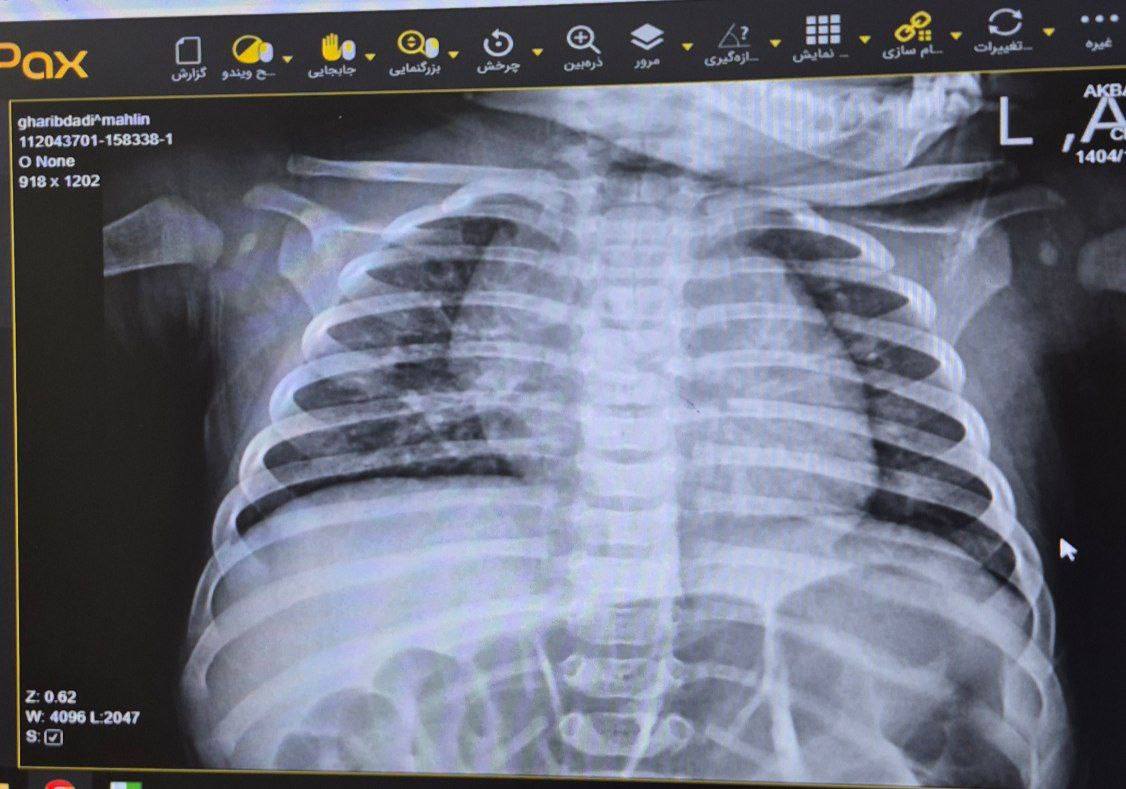

X-Ray: